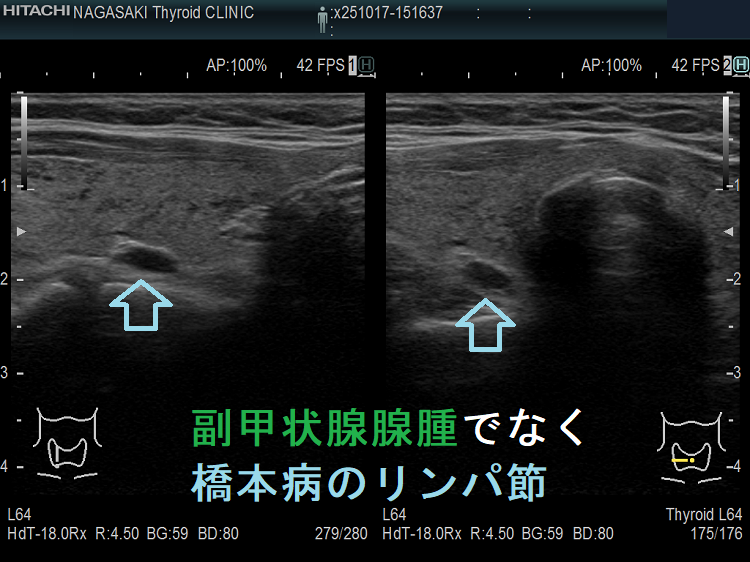

副甲状腺腺腫のように見えるも、実はただのリンパ節

副甲状腺腺腫との違いとして、リンパ節では

- 内部血流が無く

- リンパ門が存在します(ここだけ血流があります)

ケース①②